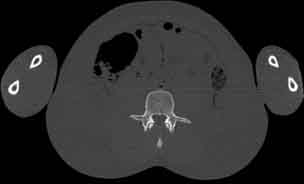

Visible Human male: Sectio transversalis 1708

CT

NMR

Pd                          / T2 \                         T1